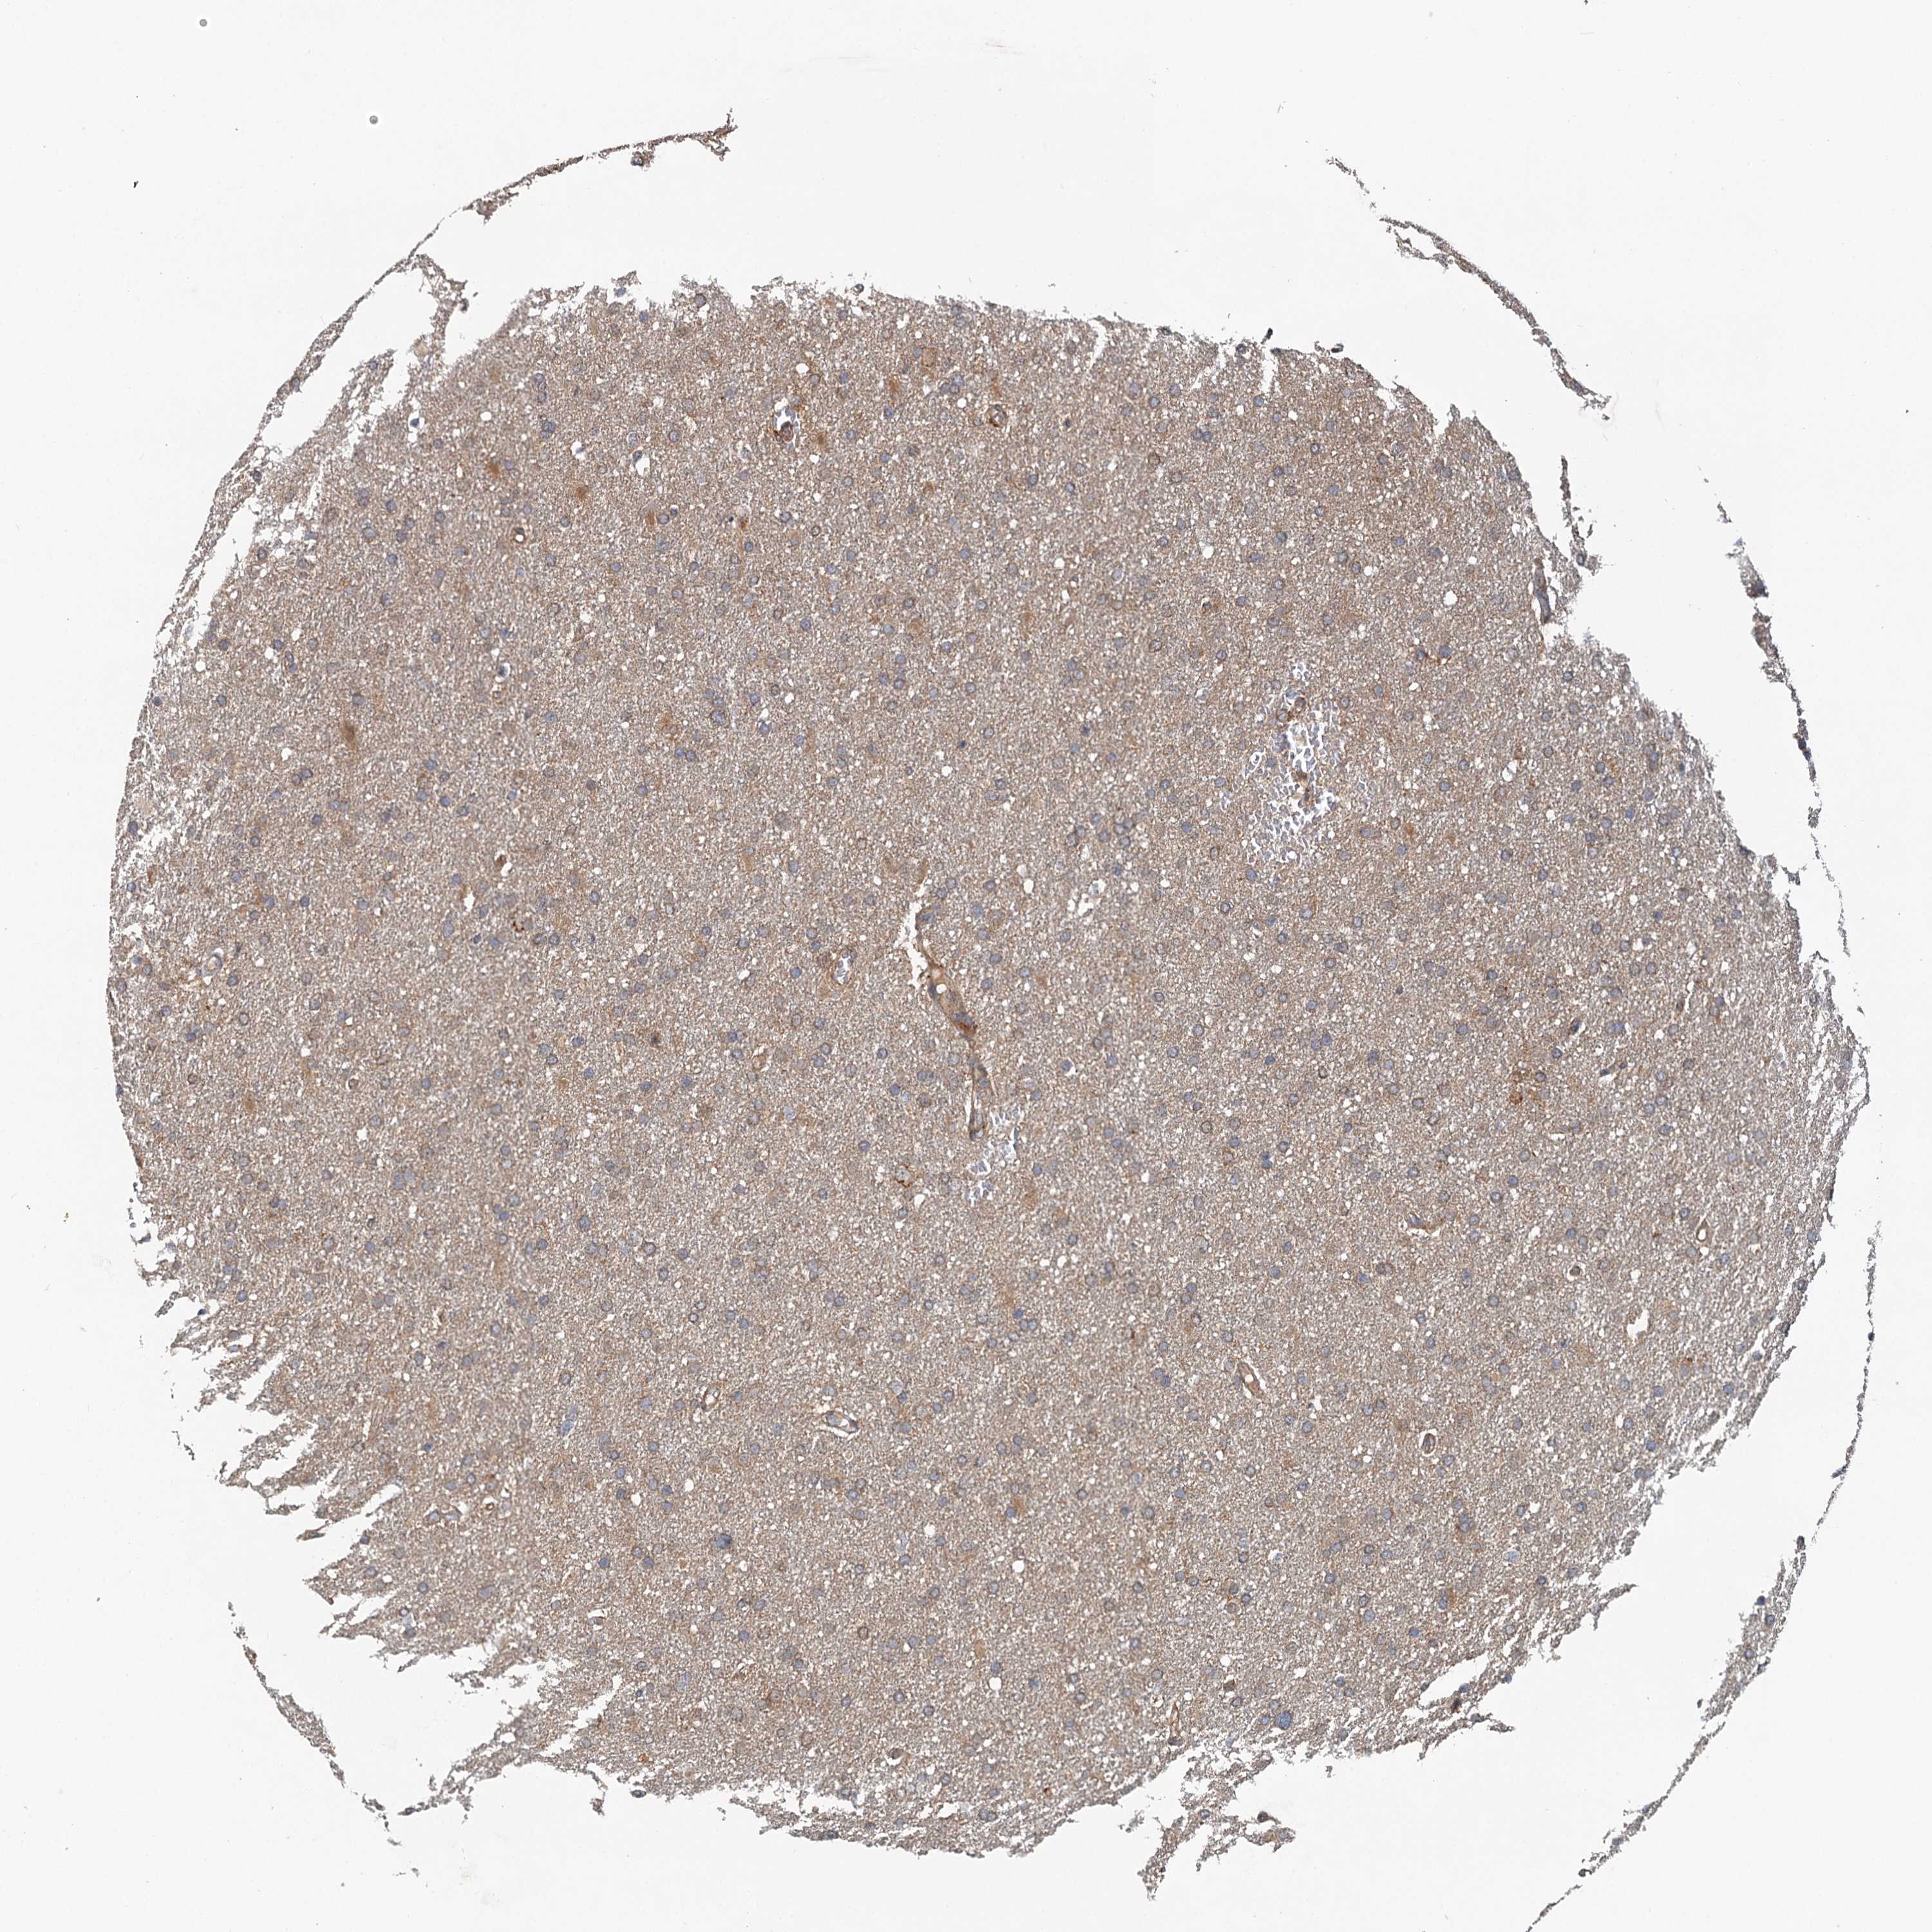

GLIOMA - Protein expressioni

A mouse-over function shows sample information and annotation data. Click on an image to view it in a full screen mode. Samples can be filtered based on level of antibody staining by selecting one or several of the following categories: high, medium, low and not detected. The assay and annotation is described here.

Note that samples used for immunohistochemistry by the Human Protein Atlas do not correspond to samples in the TCGA dataset.

Antibody stainingi

Antibody staining in the annotated cell types in the current human tissue is reported as not detected, low, medium, or high, based on conventional immunohistochemistry profiling in selected tissues. This score is based on the combination of the staining intensity and fraction of stained cells.

Each image is clickable and will lead to virtual microscopy that enables deeper exploration of all samples and also displays staining intensity scores, fraction scores and subcellular localization as well as patient and tissue information for each sample.

Antibody HPA014293

Antibody CAB037160

Staining

High

Medium

Low

Not detected

Intensity

Strong

Moderate

Weak

Negative

Quantity

>75%

75%-25%

<25%

None

Location

Nuclear

Cytoplasmic/membranous

Cytoplasmic/membranous,nuclear

Glioma, malignant, High grade

Glioma, malignant, Low grade